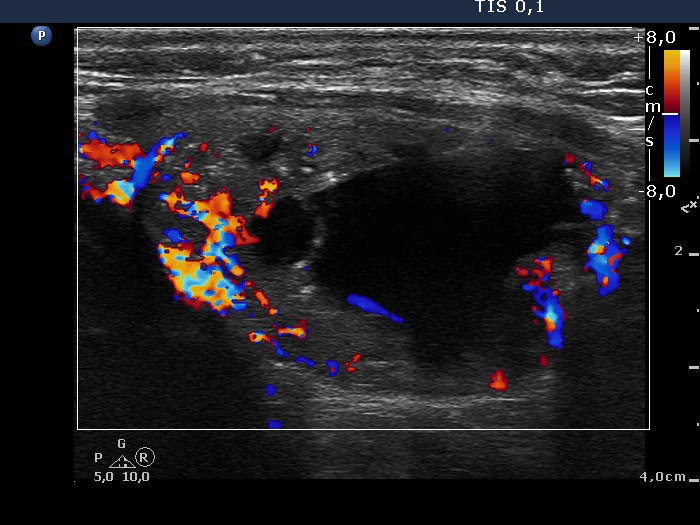

Right lobe, longitudinal scan

Left lobe, longitudinal scan, color Doppler mode. The lesion has both perinodular and intranodular blood flow.